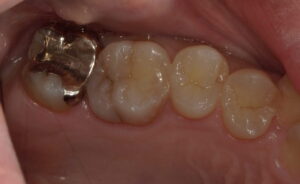

20代男性。検診希望で来院されました。上顎左側第一大臼歯遠心がなんとなく黒ずんでいます。